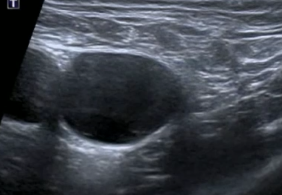

Hernie fémorale

Technique

- Permet de tester le valsalva

- Repères anatomique

- Vx fémoraux

- Muscle pectiné

crural crurale femoral

Test du valsalva

Hernie fémorale